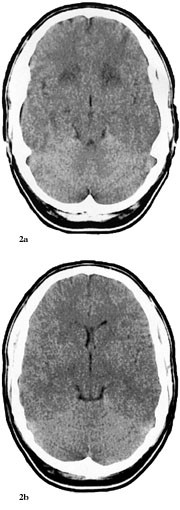

Pasient 2. En tidligere frisk 22 år gammel mann fikk i andre delen av mai 2000 halsbetennelse og tok penicillin. 31.5. utviklet han utydelig språk og kvalme. Dagen etter fikk han hodepine, han var trett og fikk hukommelsesproblemer. Ved innleggelse i lokalsykehuset var han ikke orientert, hadde amnesi for en uke tilbake, ellers var det normale nevrologiske funn. I vennekretsen hadde det forekommet tilfeller av infeksiøs mononukleose like før, men pasienten hadde verken forstørrede lymfeknuter, forstørret milt eller lever. CT med og uten kontrast var initialt vurdert som upåfallende, til tross for lettgradig asymmetri av sideventriklene (fig 1a). Infeksjonsparametere var uten anmerkning. 2.6. ble han utskrevet i velbefinnende. I løpet av de neste to dager virket pasienten eiendommelig, med humørsvingninger. 4.6. fikk han et generalisert tonisk-klonisk anfall og ble på nytt innlagt i lokalsykehuset. Tilstanden var vurdert som utløst av abstinensanfall etter moderat alkoholinntak. 5.6. ble han febril (39,0 ˚C), trett og fikk økende hukommelsesproblemer. Spinalvæskefunnet viste 7 × 10⁶ celler/l, protein 0,45 g/l, glukose 4,1 mmol/l; CRP var 21 mg/l, ASAT 31 U/l, ALAT 51 U/l, øvrige serumverdier var normale.

Pasienten ble overflyttet til Namdal Sykehus 6.6. Han var somnolent, desorientert og gav stereotype svar. Han hadde ingen fokale utfall. På mistanke om herpes simplex-encefalitt ble det iverksatt behandling med aciklovir 3 ⋅ 750 mg intravenøst, i tillegg fenytoin 2 ⋅ 250 mg intravenøst mot symptomatiske epileptiske anfall. Dagen etter ble pasienten soporøs. EEG var preget av en generalisert langsom aktivitet, delvis i form av bilateral synkron, rytmisk deltaaktivitet (frontal intermittent rhythmic delta acitvity, FIRDA). CT viste symmetriske forandringer i basalgangliene og basale deler av cerebrum som var ødematøs (fig 2a, 2b). En ny spinalvæskeprøve, tatt 8.6., viste 17 celler. En CT fra 9.6. viste progredierende forandringer (fig 3).

Dessverre hadde vi ingen mulighet til å få utført MR og obduksjon. Likevel er en akutt demyeliniserende encefalomyelitt mindre sannsynlig på grunn av at sykdomsutviklingen ikke kom helt akutt, men var gradvis innsettende i løpet av ti dager. Dessuten hadde man ikke fokale eller multifokale motoriske eller sensible utfall (10, 13). CT-funn viste progredierende, symmetriske forandringer som gav hypodensitet først i basalganglier og senere generelt, men hele tiden mest i basale deler av storehjernen og i de limbiske strukturer (fig 1 – 3). Retrospektivt aner man allerede ved første CT-undersøkelse (fig 1b) små hypodense områder ut for 3. ventrikkel på hver side lavt i basalgangliene. Disse funnene tyder heller på en atypisk encefalitt enn på en akutt demyeliniserende encefalomyelitt og korresponderer med de kliniske funn av hukommelsesproblemer og personlighetsforandringer. Pasienten fikk terminalt sentral respirasjonsstans, noe som kan tyde på hjernestammeaffeksjon.